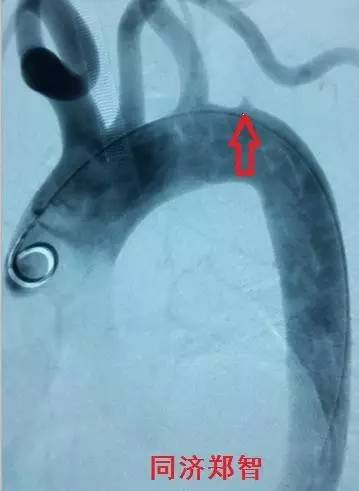

DSA造影显示降主动脉穿透性溃疡(图8)。

图8